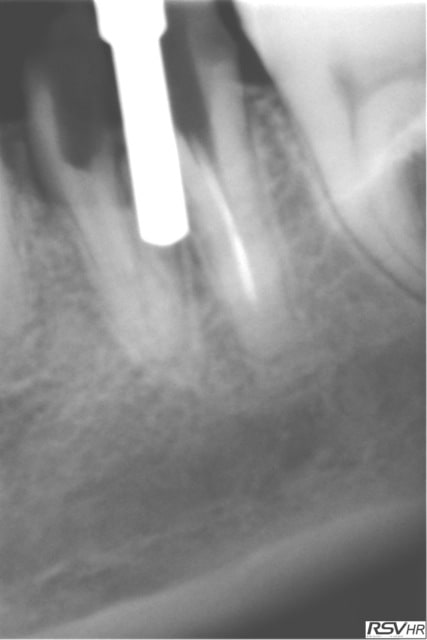

même patiente pour 46

extraction le 31.03.2012 avec le même jour pose implant legacy

cette fois long10mm diamètre 4.7mm

toujours la technique forage entre racines extraction reforage pose implant

le 13.09.2012 couronne céramométallique sur fM